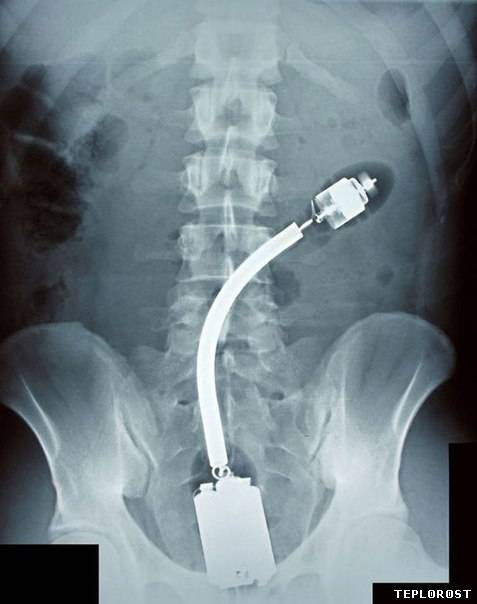

Полицейская дубинка в заднем проходе пациента.